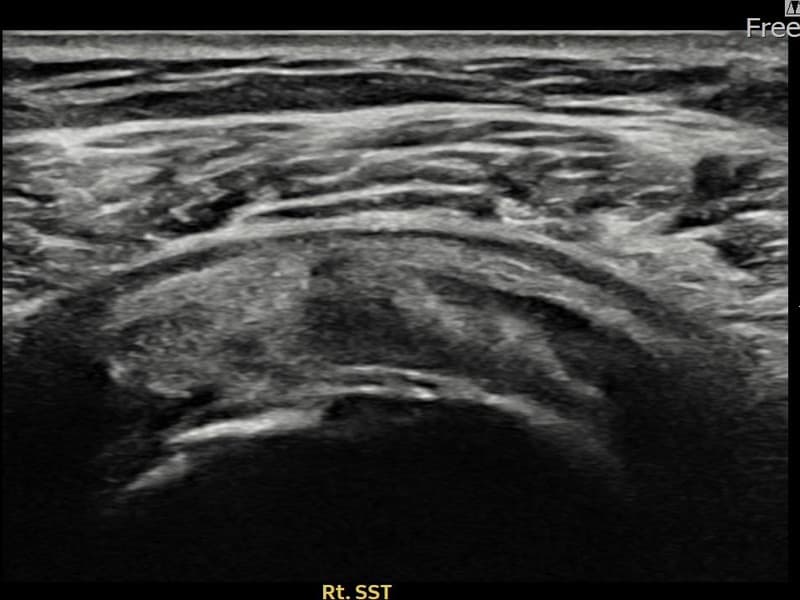

시술 전 초음파 측정 결과 파열 크기는 7mm × 3mm (힘줄 두께의 약 30% 결손)로 확인되었습니다. 시술 전 초음파에서 우측 극상근건 관절면측의 에코 단절과 힘줄 결손 소견이 확인되었습니다. 시술 후 초음파에서 파열 부위에 재생 조직이 형성되고 힘줄 연속성이 회복된 것이 관찰되었습니다.

60대 초반 여성 환자분으로, 집안일과 텃밭 작업을 꾸준히 하시다가 우측 어깨 통증이 서서히 심해져 내원하셨습니다. 팔을 60~120도 구간에서 들어 올릴 때 충돌 통증이 심하고, 야간에도 어깨를 짓누르는 듯한 통증이 있어 수면에 지장이 있으셨습니다. 초음파 검사에서 우측 극상근건 관절면측 부분파열이 확인되었으며, 힘줄 내 에코 단절이 뚜렷한 상태였습니다. 수술 없이 초음파 유도 하 축소봉합술을 시행하였고, 당일 귀가 후 재활 운동을 단계적으로 진행하셨습니다. 시술 11주 후 추적 초음파에서 파열 부위 연속성이 회복되고 충돌 증상이 소실되어 정상 생활에 복귀하셨습니다.